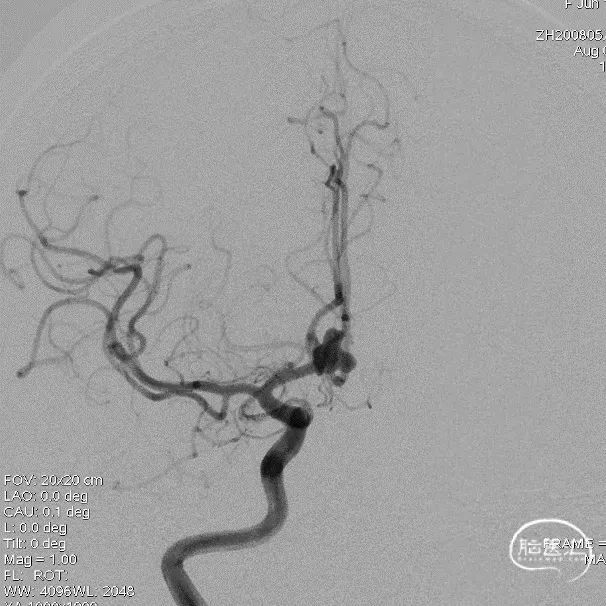

术前影像

术前影像

术前影像